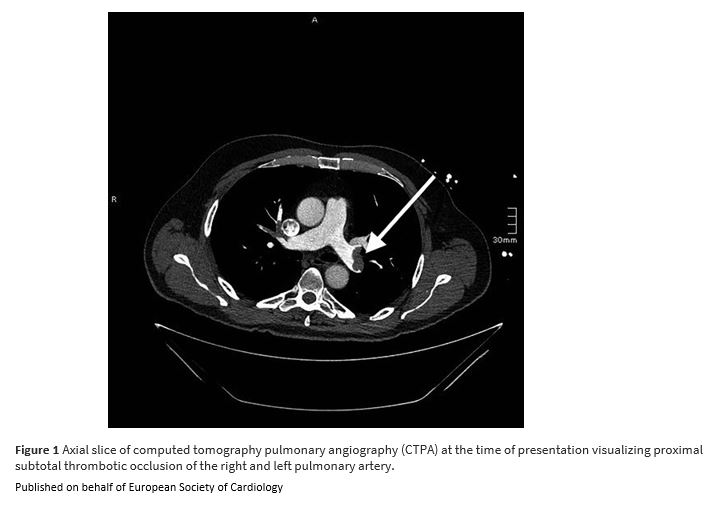

Unexpected paradoxical embolisation following catheter-directed thrombectomy with the FlowTriever™ system in a case of pulmonary embolism bit.ly/41n1RlZ

#EHJCaseReports #EchoFirst @aayshacader @KardiologieHH @ANazmiCalik @EHJCREiC @TJ_Yeo @Phiso_de @FarhanaAra